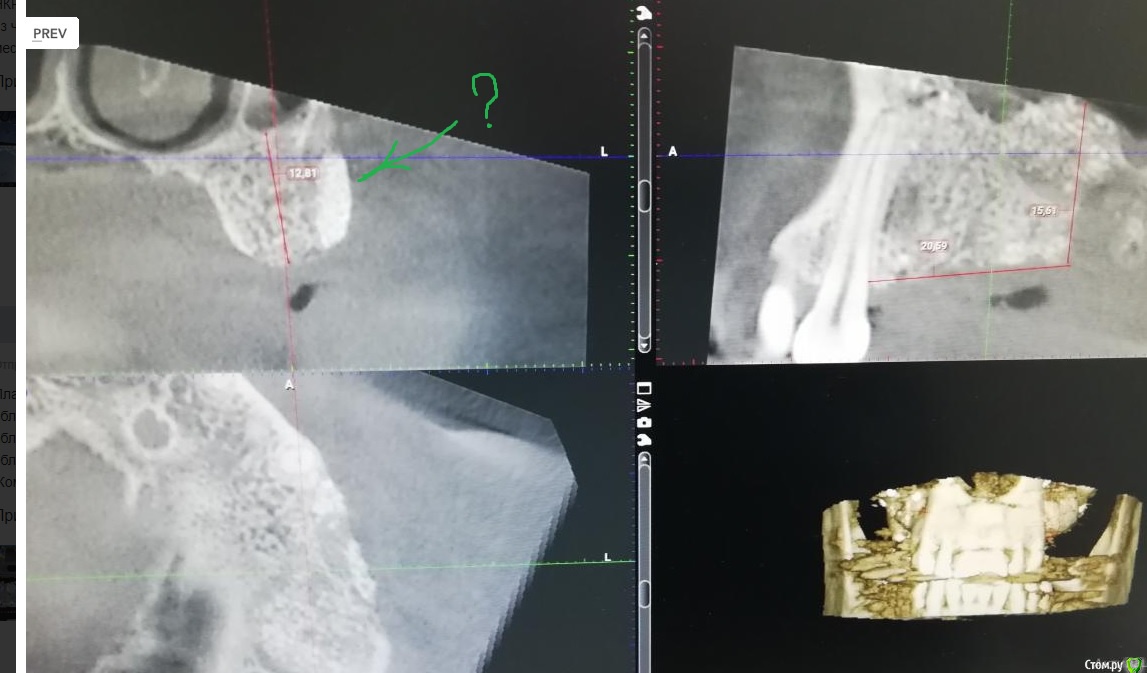

___49___ Опубликовано 23 декабря, 2019 Поделиться Опубликовано 23 декабря, 2019 (изменено) 6 месяцев назад , проведено РВК двух корней 14 зуба с ретроградкой триоксидентом, в дефект заложена гемостатическая губка на линкомицине, в месте доступа подсыпан чистый ксено с излишком . Синуслифтинг в области 16 и 15 го отсутствующих зубов , Ксено +ауто и под них 3 губки на линкомицине (участок с молодыми костными балками без ксено на фото - между графтом и старой границей кости ) . Область окна при синусе и немного вестибулярнее смесь ксено + ауто с излишком ( как говорил учитель если есть ширина то будет и высота , в том числе и как опора для мягкотканной пластики если понадобится ) . все перекрыто резорбируемой мембранной на пинах. Азитромицин перед операцией . Изменено 23 декабря, 2019 пользователем ___49___ 1 Ссылка на комментарий

___49___ Опубликовано 23 декабря, 2019 Автор Поделиться Опубликовано 23 декабря, 2019 НКР вестибулярно в области 24 зуба ксено +ауто, НКР вертикально в области 26го зуба ксено +ауто(утрамбовано очень плотно) , Синуслифт в области 26 и 25 го ксено +ауто, из чистого ксено сделана боковая поддержка вестибулярно для будущих мягких тканей в области 26 и 25 , все перекрыто резорбируемой мембраной на пинах.. Через 4.5 месяца удален 27 ой зуб , заложена губка плотно ( уже появляются первые балочки на Rg). 1 Ссылка на комментарий

___49___ Опубликовано 23 декабря, 2019 Автор Поделиться Опубликовано 23 декабря, 2019 Планирую Импланты:обл16 - 6х8 обл 24- 4.5х12обл 26- 6х12 Коментарии, критика , свое виденье планирования уважаемые коллеги высказывайте. Спасибо . Ссылка на комментарий

___49___ Опубликовано 23 декабря, 2019 Автор Поделиться Опубликовано 23 декабря, 2019 Сам из косяков вижу - не достаточную отслойку шнайдера в области 26го ближе к носовому ходу. Ссылка на комментарий